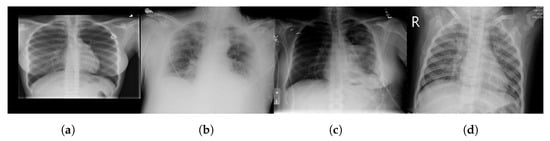

The chest X-ray dataset encompasses a larger collection of 3616 images. These images are chest X-rays (Figure 3)—a fundamental diagnostic tool widely used in clinical practice. This dataset reflects a diverse range of medical conditions, including those related to COVID-19 [83], and includes a variety of anatomical regions within the chest.

Figure 3.

Sample chest X-ray images with different classes: (a) normal, (b) COVID-19, (c) lung opacity, and (d) pneumonia.

As mentioned above, we chose datasets with different characteristics and challenges to evaluate our method’s performance. The chest X-ray dataset, for instance, consists of 2D X-ray images of the chest. These images introduce a unique set of challenges, characterized by lower spatial resolution and the presence of overlapping structures such as ribs and organs. Moreover, these images, relevant to COVID-19 diagnosis, might exhibit specific patterns associated with viral pneumonia, adding another layer of complexity to the segmentation process.